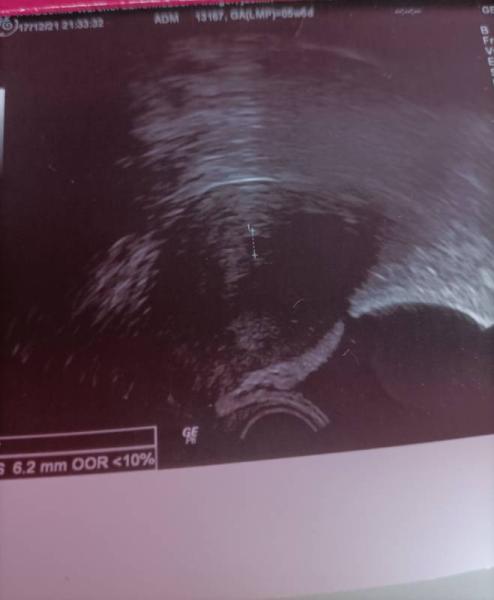

Hallo zusammen:) Bin laut App bei 5+1, laut dem US heute bei 5+6.... Ich habe schon viele Ultraschallbilder dieser Woche in der Hand gehabt aber irgendwie verunsichert mich mein eigenes.....dort ist so viel schwarze Fläche das kenne ich so gar nicht... Laut Gyn ist alles super. Habt ihr denn auch Mal ein so undeutliches Ultraschallbild gehabt oder kann mir jemand verraten wieso da so viel schwarz ist? Viele Grüße :)

Hallo Herzlichen Glückwunsch erstmal. Lass dich nicht verunsichern, die Bildqualität ist stark von dem Gerät und den Lichtverhältnissen abhängig. Du bist derzeit bei 5+6 das ist auch noch sehr früh um mehr im US zu sehen. Solange deine FÄ zufrieden ist, ist doch alles super